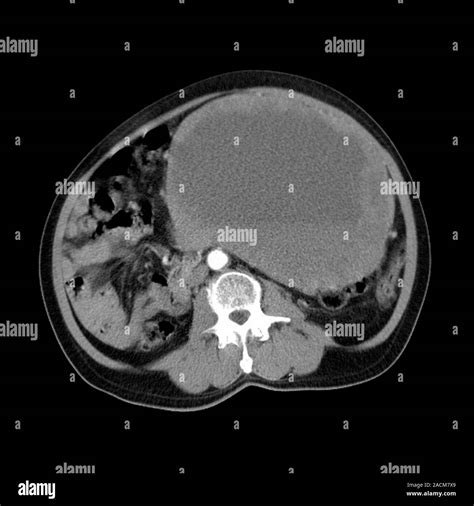

CT Scan High-resolution cross-sectional images to pinpoint the exact location and nature of the mass.

Because the abdomen contains a dense arrangement of structures, relying on a physical "self-exam" is rarely sufficient. A doctor will typically correlate physical findings with diagnostic imaging. For instance, an ultrasound might distinguish between a solid tumor and a fluid-filled cyst, while a CT scan provides the necessary detail to assess whether the mass in stomach involves surrounding blood vessels or lymph nodes. In some cases, a biopsy—the removal of a small tissue sample—is the only definitive way to characterize the cellular nature of the mass.